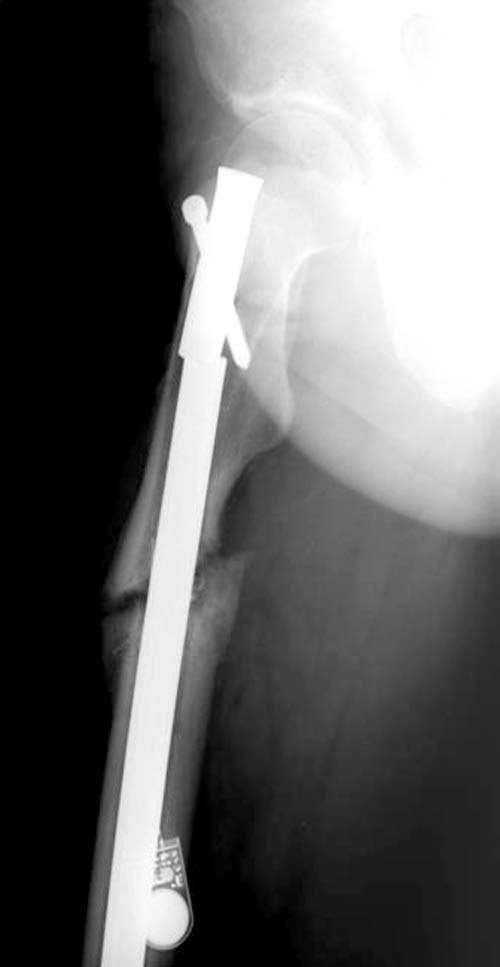

Надо удалить стержень, восстановить длину бедра (одномоментно или постепенно), и вновь синтезировать стержнем. На этот раз правильно расположив его в проксимальном отломке.

Для чего из этой же точки входа надо его направить в сторону латеральной стенки костной трубки. Для этого ввести 2-3 отклоняющих спицы в передне-заднем направлении в проекции нынешнего положения гвоздя. Чтобы гвоздь ушел латеральнее этих спиц. Можно ввести и спицу фронтально, чтобы гвоздь направить к передней стенке центрального отломка. Получится хороший контакт латеральных стенок основных отломков. И мысли про костную пластику рассеются, как туман над Днепром после восхода солнца.

Тактика замены на более толстый гвоздь вроде правильная, и возможно у Вас получится с первого раза. Но без специальных трюков гвоздь удержать трудно, потому что между точкой на верхушке трохантера и старым каналом в пириформис почти отсутствует стенка. Без стенки трудно удержать гвоздь латерально и без блокирующих приспособлении гвоздь найдет старый канал. Конечность поведет и винт в головке срежется. Без опыта проведении блокирующих спиц, о которых говорит Александр, вся затея окажется фиаско! Отклоняющие в передне-заднем направлении спицы в проксимальном отделе бедра немного страшновато, с повреждением седалищного нерва!

Согласен с Александром Николаевичем. Мне кажется, лучше операцию выполнить в два этапа, не первом наложив спице-стержневой аппарат для дистракции. Это позволит малотравматично и закрыто! (что почти невозможно при одномоментном устранении укорочения, т.к. за 1 год и 3 мес сформировались очень плотные рубцы и ретракция мышц) устранить захождение отломков. А это значительно упростит правильную установку штифта, что, в свою очередь, минимизирует риск осложнений после операции.